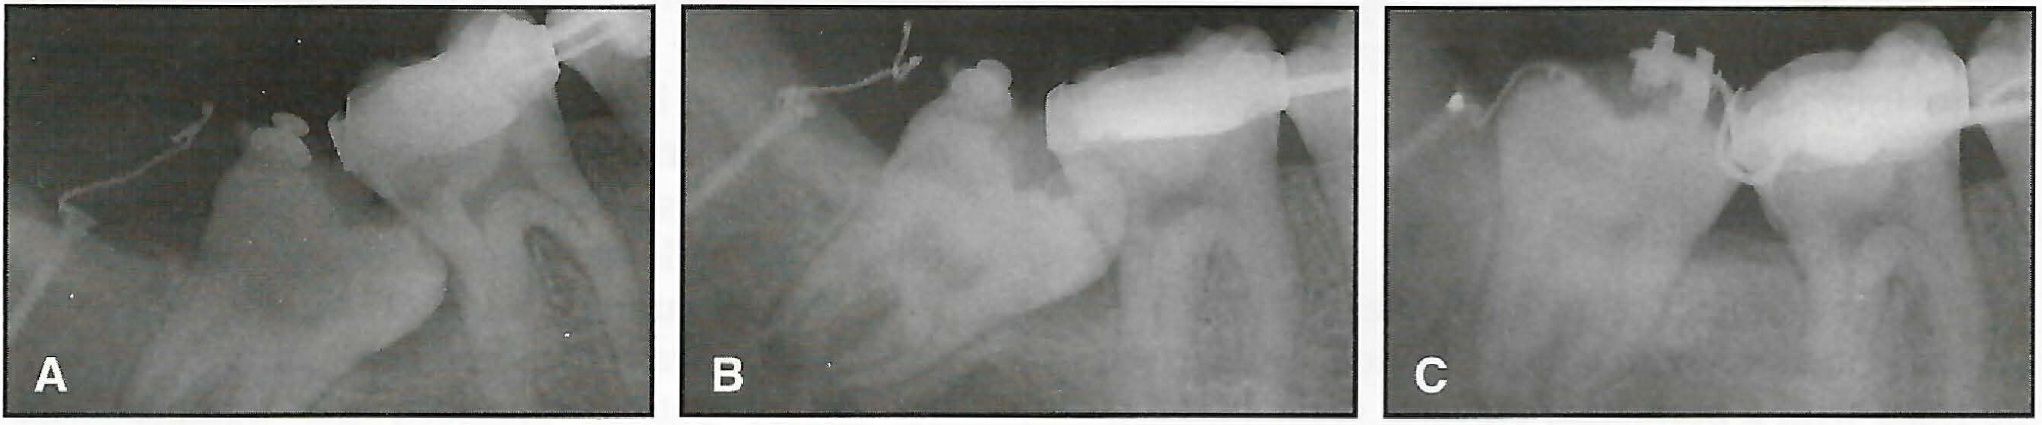

Initial .016" Australian archwires with strong bite-opening bends mesial to the molar tubes were placed in both arches (Fig. 16A). The patient was instructed to wear light (1.5oz) Class II elastics full-time. Cooperation was poor during the first few months, but improved thereafter.

Within eight months, the overbite, overjet, and Class II molar relationship had been corrected. Stage III, delayed by the slow eruption of the maxillary second premolars, was begun after 17 months (Fig. 16B).

Eight months later, all root uprighting and torquing was complete and the appliances were removed (Fig. 16C). A tooth positioner was delivered for retention. Treatment was accomplished in about 26 months using only four straight archwires (two .016'' for Stage I and two .022" for Stages II and III).

Fig. 16 Case 2. A. Six weeks after placement of initial .016" archwires with bite-opening bends. B. Beginning of Stage III. C. After 26 months of treatment.